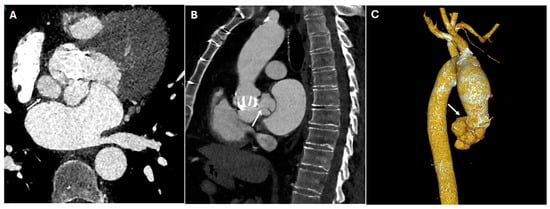

| Endoleaks (TEVAR) | Incomplete sealing, graft migration | Persistent contrast enhancement outside stent graft lumen | Can lead to aneurysm expansion and rupture |

| Graft Migration (TEVAR) | Insufficient landing zone, poor fixation | Displacement > 10 mm on sequential imaging | May cause endoleaks or malperfusion |

| Graft Occlusion (TEVAR) | Thrombosis, intimal hyperplasia | Lack of contrast opacification within the graft, collateral vessel formation | May result in ischemia |

| TEVAR | Descending aortic aneurysms, dissections | Endovascular stent placement | High-density metallic structure conforming to aortic lumen |